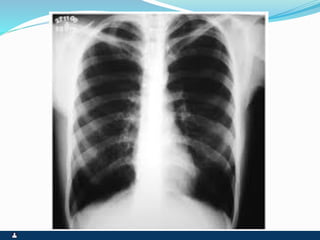

RAREFAÇÃO PARENQUIMATOSA

ENFISEMA

SINTOMAS SINAIS

 MAGRO, LONGILÍNEO –

PINK PUFFER

 TOSSE SECA OU POUCO

PRODUTIVA

 DISPNÉIA PROGRESSIVA

AOS ESFORÇOS

 ANCORAGEM

 TORAX EM TONEL

 ESFORÇO RESPIRATÓRIO

 TIRAGEM

 EXPANSIBILIDADE REDUZIDA

 FTV REDUZIDO

 HIPERSONORIDADE

 MV REDUZIDO, COM TEMPO

EXPIRATÓRIO AUMENTADO

 POUCOS RUIDOS

ADVENTÍCIOS